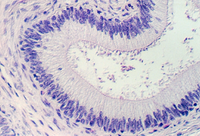

The Prostate epithelium looks cuboidal or pseudostratified low columnar in spots. Inside the glandular lumena you may see laminated bodies known as concretions. These are evident in the following photograph and help identify the organ as the prostate.

In the connective tissue there are bundles of smooth muscle which stand out

because of their homogeneous cytoplasm. Find smooth muscle in the above photograph

or the one below. What components of semen are contributed by the prostate?